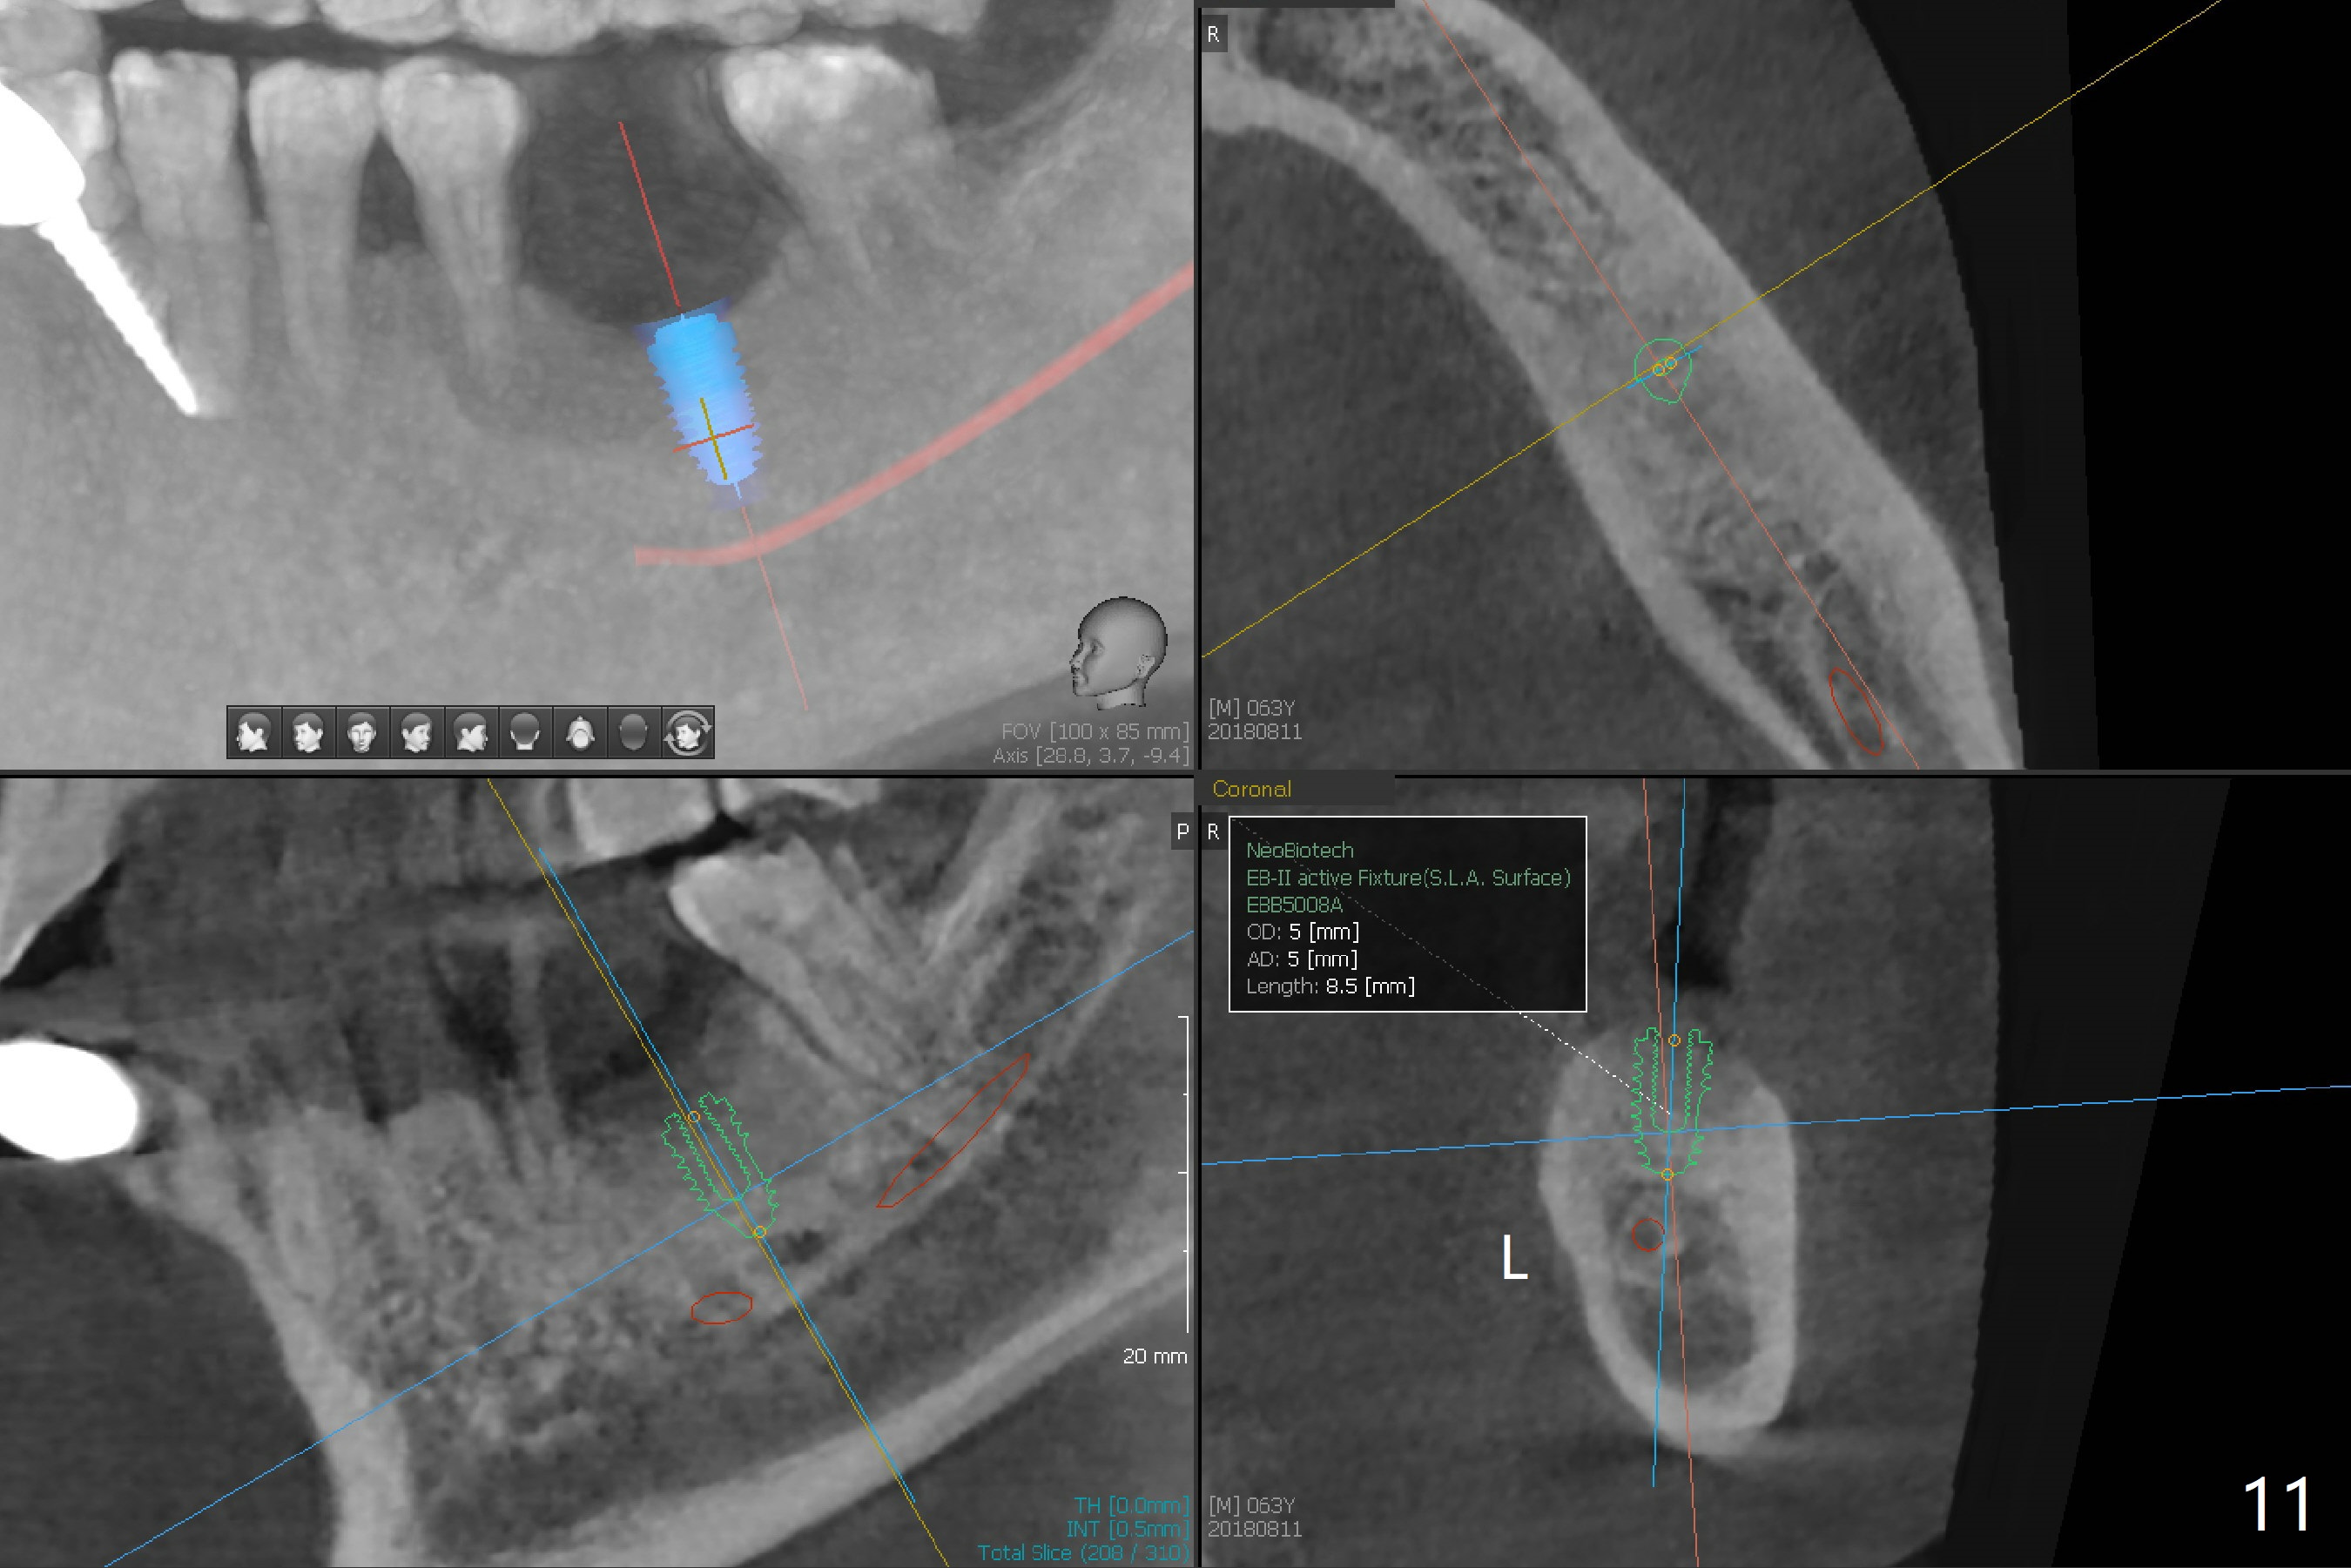

A 63-year-old man is a diabetic with history of good control. He masticates unilaterally with missing teeth #2,3 and 24 (Fig.1 (taken 5 years ago)). The latter has been restored with an implant. Last February the mesial root of the tooth #19 was found to have vertical fracture with bone loss until the base of the septum (Fig.2). The bone available for implantation is ~7-8 mm after root fracture (Fig.3,4). The initial osteotomy depth will be 7 mm (IS kit), followed by the calibrated parallel pin. The latter determines how many millimeters of an implant will be surrounded by the graft bone (Fig.4,5 (green: implant length; pink: cuff; blue: abutment length)). Since the buccal defect is severe with mesial root split (Fig.7 *), draw blood for PRF (2 large tubes). To save the remaining septum, place 2 of 1-piece implants on the either side of the septum (compare Fig.6,8). Take photos to compare buccal vs. lingual gingival recession. Tell the patient that the tooth #20 may be nonsalvageable. Since insurance preauthorization does not get approval for several times, the tooth #19 is extracted with socket preservation and periodontal dressing. The latter dislodges in 1 day. When the patient returns for follow up 4 days postop, the socket is exposed (Fig.9). An immediate implant should have been placed to keep the graft in place. PRF also helps. In fact preauthorization letter arrived 1 day earlier. It appears that guided surgery is indicated for limited bone height. The bone graft appears to gain ~ 5 mm bone in 4 months (Fig.10), which allows to place a 5x8.5 mm implant (Fig.11).